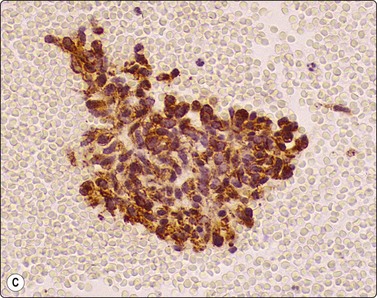

image image image

Fig. 8.28 High-grade neuroendocrine carcinoma; small cell carcinoma

(A, B) Smears showing ‘intermediate’ morphology. Loose aggregates of fragile cells with traumatization artifact and nuclear molding but some background cytoplasm (A, Pap, MP; B, H&E, HP). (C) Tissue section of resected peripheral stage 1 small cell carcinoma (H&E, HP).

image image image image image

Fig. 8.29 High-grade neuroendocrine carcinoma

Variable morphology including small cell and large cell patterns. (A) Low-power smear appearances of small cell carcinoma; (B) Higher-power examination shows some large cells with prominent nucleoli (A, H&E, LP; B, H&E, MP). (C,D) Tissue sections of resected peripheral stage 1 tumor showing areas of geographic necrosis and a predominance of large cells with prominent nucleoli (C, tissue section, H&E, LP, Inset, HP; D, tissue section, H&E, HP). (E) Positive immunostaining for chromogranin in resected specimen (E, tissue section, IPOX, HP).

Although ‘intermediate’ small cell carcinoma is no longer recognized as a separate category in international classifications, we find it a useful concept to highlight the occasional difficulty in distinguishing between small cell and poorly differentiated non-small cell carcinomas (Figs 8.28 and 8.29). There is overlap in nuclear size between small and large cell carcinomas and a tendency for inexperienced cytologists to include small cell carcinomas with larger than expected nuclei in the non-small cell category. In general, if the nuclear features of a problematical tumor are those of small cell carcinoma – that is, granular chromatin without prominent nucleoli – the neoplasm will usually fall into the small cell carcinoma group histologically, whereas vesicular nuclei with prominent nucleoli would generally be evidence of non-small cell tumor. However, large cell neuroendocrine carcinoma does provide special problems. Our experience is limited but is similar to Yang et al. who described various morphologic patterns in this family of tumors, including small cell-like and mixed small cell/large cell-like FNAC patterns.37 Cell size is therefore an important criterion and one to be critically evaluated. Tumors with nuclei larger than 2–3 times the diameter of a lymphocyte may be classified as LCNEC histologically, even if nuclear chromatin pattern and other cytological features are similar to those of small cell carcinoma (Fig. 8.29). Our approach is therefore to first come to a diagnosis of ‘high-grade neuroendocrine carcinoma’ and then to critically examine cell size and morphology to determine the best category – ‘small’ or ‘large’. We do, however, agree with the idea propounded by Marchevsky et al.89 that the distinction between the two categories may be somewhat artificial in view of the overlap in cell size between the two groups. This is an area which requires close cooperation with oncologists and an acceptance of the limitations of cytological diagnosis. It may be necessary to base management on clinical and staging findings in conjunction with inconclusive cytological tumor typing in some cases.